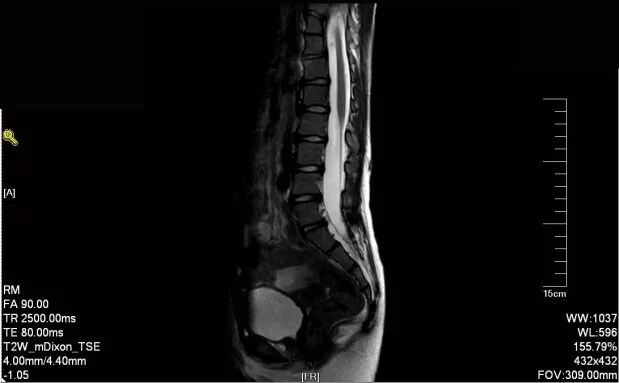

多节段腰椎峡部裂伴滑脱需要手术吗

图片尺寸752x404